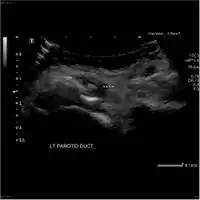

-

Acute left parotid sialadenitis -

Acute left parotid sialadenitis